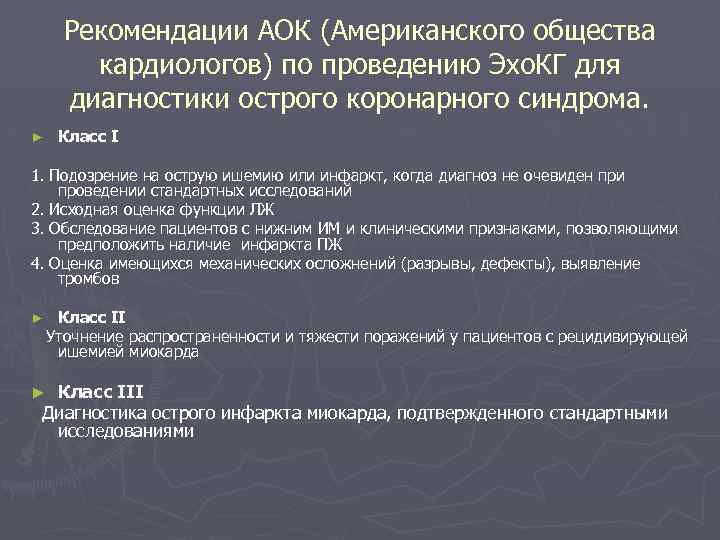

Рекомендации АОК (Американского общества кардиологов) по проведению Эхо. КГ для диагностики острого коронарного синдрома. Класс I ► 1. Подозрение на острую ишемию или инфаркт, когда диагноз не очевиден при проведении стандартных исследований 2. Исходная оценка функции ЛЖ 3. Обследование пациентов с нижним ИМ и клиническими признаками, позволяющими предположить наличие инфаркта ПЖ 4. Оценка имеющихся механических осложнений (разрывы, дефекты), выявление тромбов ► Класс II Уточнение распространенности и тяжести поражений у пациентов с рецидивирующей ишемией миокарда Класс III Диагностика острого инфаркта миокарда, подтвержденного стандартными исследованиями ►